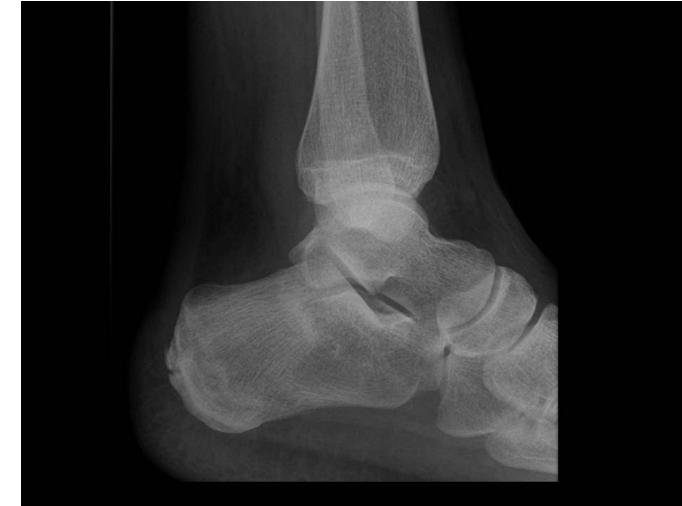

Q6/ For patients with this following fracture, you have to rule out the most associated injury which is:

- A. Spine fracture

QUESTION 9: A case about a patient who fell from a high building. โX-ray showed a calcaneus fractureโ, what is the most likely fracture to be associated with this injury?

A case about a patient who fell from a high building. โX-ray showed a calcaneus fractureโ, what is the most likely fracture to be associated with this injury?

- Spinal fracture